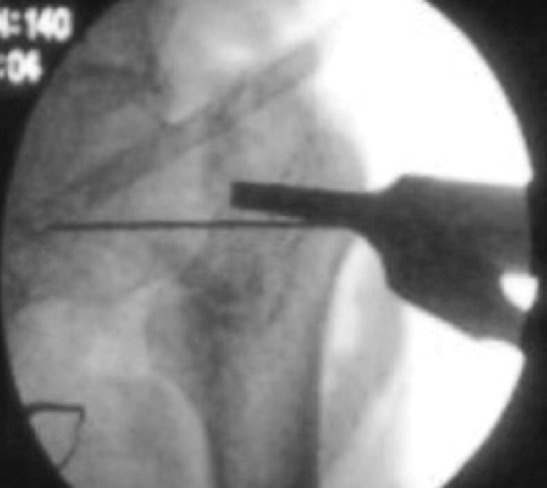

Fig. 2:

Guide wire passed parallel and inferior to the femoral neck under fluoroscopic guidance.